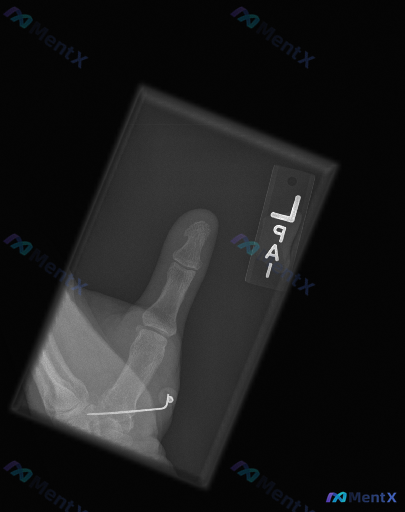

整理到一张左侧拇指的术后X光片,先放一下基础影像信息: - 部位:左侧拇指(正位) - 背景:有近期骨科手术史 - 常规报告印象:第一掌骨基底部可见内固定(克氏针)在位,未见新发骨折征象或内固定失效表现 不过这份深度分析报告里提了几个不一样的视角,甚至说「不是单纯的正常术后复查」。 想先问问大家:只...

整理了一份左手拇指区域的斜位X光病例资料,先把客观影像表现放出来: - 可见左手拇指近节、远节指骨及第一掌骨,第一腕掌关节、掌指关节、指间关节对位尚可,关节间隙宽度尚可 - 第一掌骨桡侧近基底部区域有一枚金属克氏针影,穿过第一掌骨,针尾弯曲并带有固定装置,从皮下穿出或止于皮下软组织层 - 克氏针穿行...